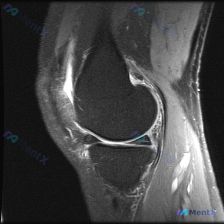

提示半月板异常的膝关节MRI,实际异常居然在这里?

看到这份有意思的病例,主诉是提示半月板异常的膝关节MRI,整理了完整的读片思路和分析,分享给大家。

这是一幅膝关节MRI T2加权矢状位图像,我们先确认基础信息:

- 成像序列符合T2WI特征:液体高信号、软骨中等信号、脂肪低信号、骨皮质及韧带低信号

- 切面展示膝关节前部结构:髌骨、髌腱、股四头肌腱、Hoffa氏脂肪垫、膝关节前间隙

- 髌骨前方软组织可见明显高信号影,提示软组织水肿或积液;髌腱走行清晰,但髌骨下极附着点处信号异常增高,符合炎症改变

- 髌下Hoffa氏脂肪垫内可见片状高信号影,提示脂肪垫水肿或炎症(Hoffitis)

- 髌股关节区域可见少许液体高信号,无大量弥漫性关节腔积液

- 髌股关节对合关系正常

拿到这份病例,第一点就是发现了矛盾:临床提示「半月板异常」,但我们看到的主要异常根本不在半月板,反而全集中在膝关节前方的软组织。

最突出的异常就是膝关节前方髌前软组织+髌下脂肪垫的局限性T2高信号,这种表现往往和膝关节前方直接撞击、反复摩擦劳损(比如频繁跪地、反复微小损伤)有关。

- 当前图像上实际存在的明确异常是髌前滑囊炎合并髌下脂肪垫炎,部分伴随髌腱炎,这是最可能的诊断

- 现有影像层面没有看到明确的半月板撕裂征象,原提示的「半月板异常」更可能是:要么是膝前软组织炎症的疼痛放射到关节线,被误判为半月板来源;要么是半月板仅有轻度退变,不是当前症状的主要原因

- 不能完全排除未在本次切面显示的半月板病变,但优先级远低于已经明确的膝前软组织病变